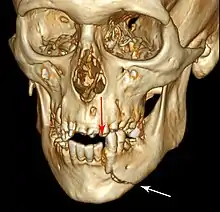

Computed tomography is the most sensitive and specific of the imaging techniques. The facial bones can be visualized as slices through the skeletal in either the axial, coronal or sagittal planes. Images can be reconstructed into a 3-dimensional view, to give a better sense of the displacement of various fragments. 3D reconstruction, however, can mask smaller fractures owing to volume averaging, scatter artifact and surrounding structures simply blocking the view of underlying areas.

- 3D CT reconstruction of mandible fracture, white arrow marks fracture, red arrow marks moderate displacement and open bite